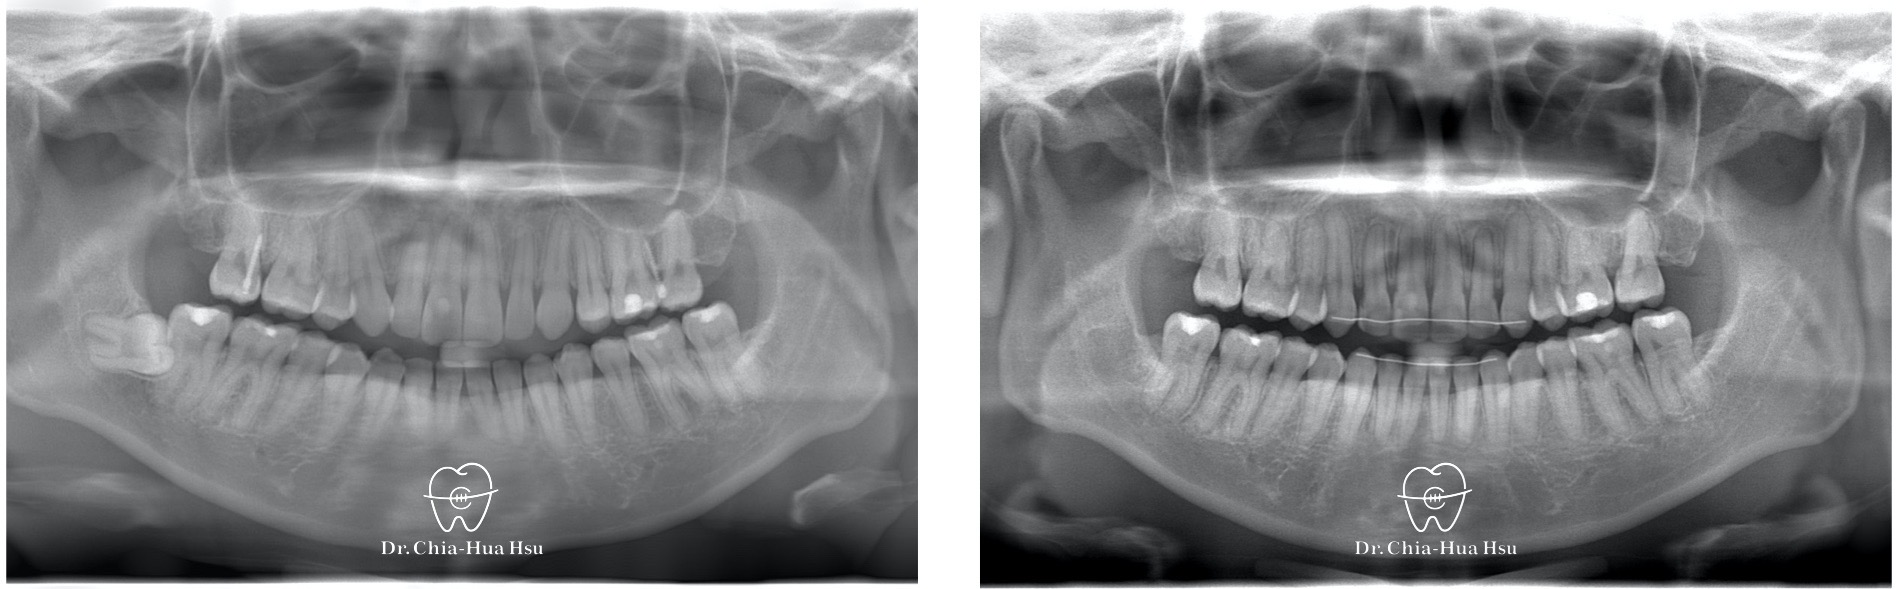

- 患者最初是暴牙,在其他診所做了三年的矯正治療後,被做成前牙反咬,與前一位醫師溝通不順利,於是再次尋求矯正治療。

- 病患主訴:前牙錯咬、再次矯正治療。

- 問題分析:患者有前牙錯咬(反咬)、後牙錯咬的問題。

- 治療方式:使用傳統金屬矯正器,使用原有骨釘將上顎牙齒前移,迅速將療程結束。

- 治療時間:1 年 3 個月。

治療前